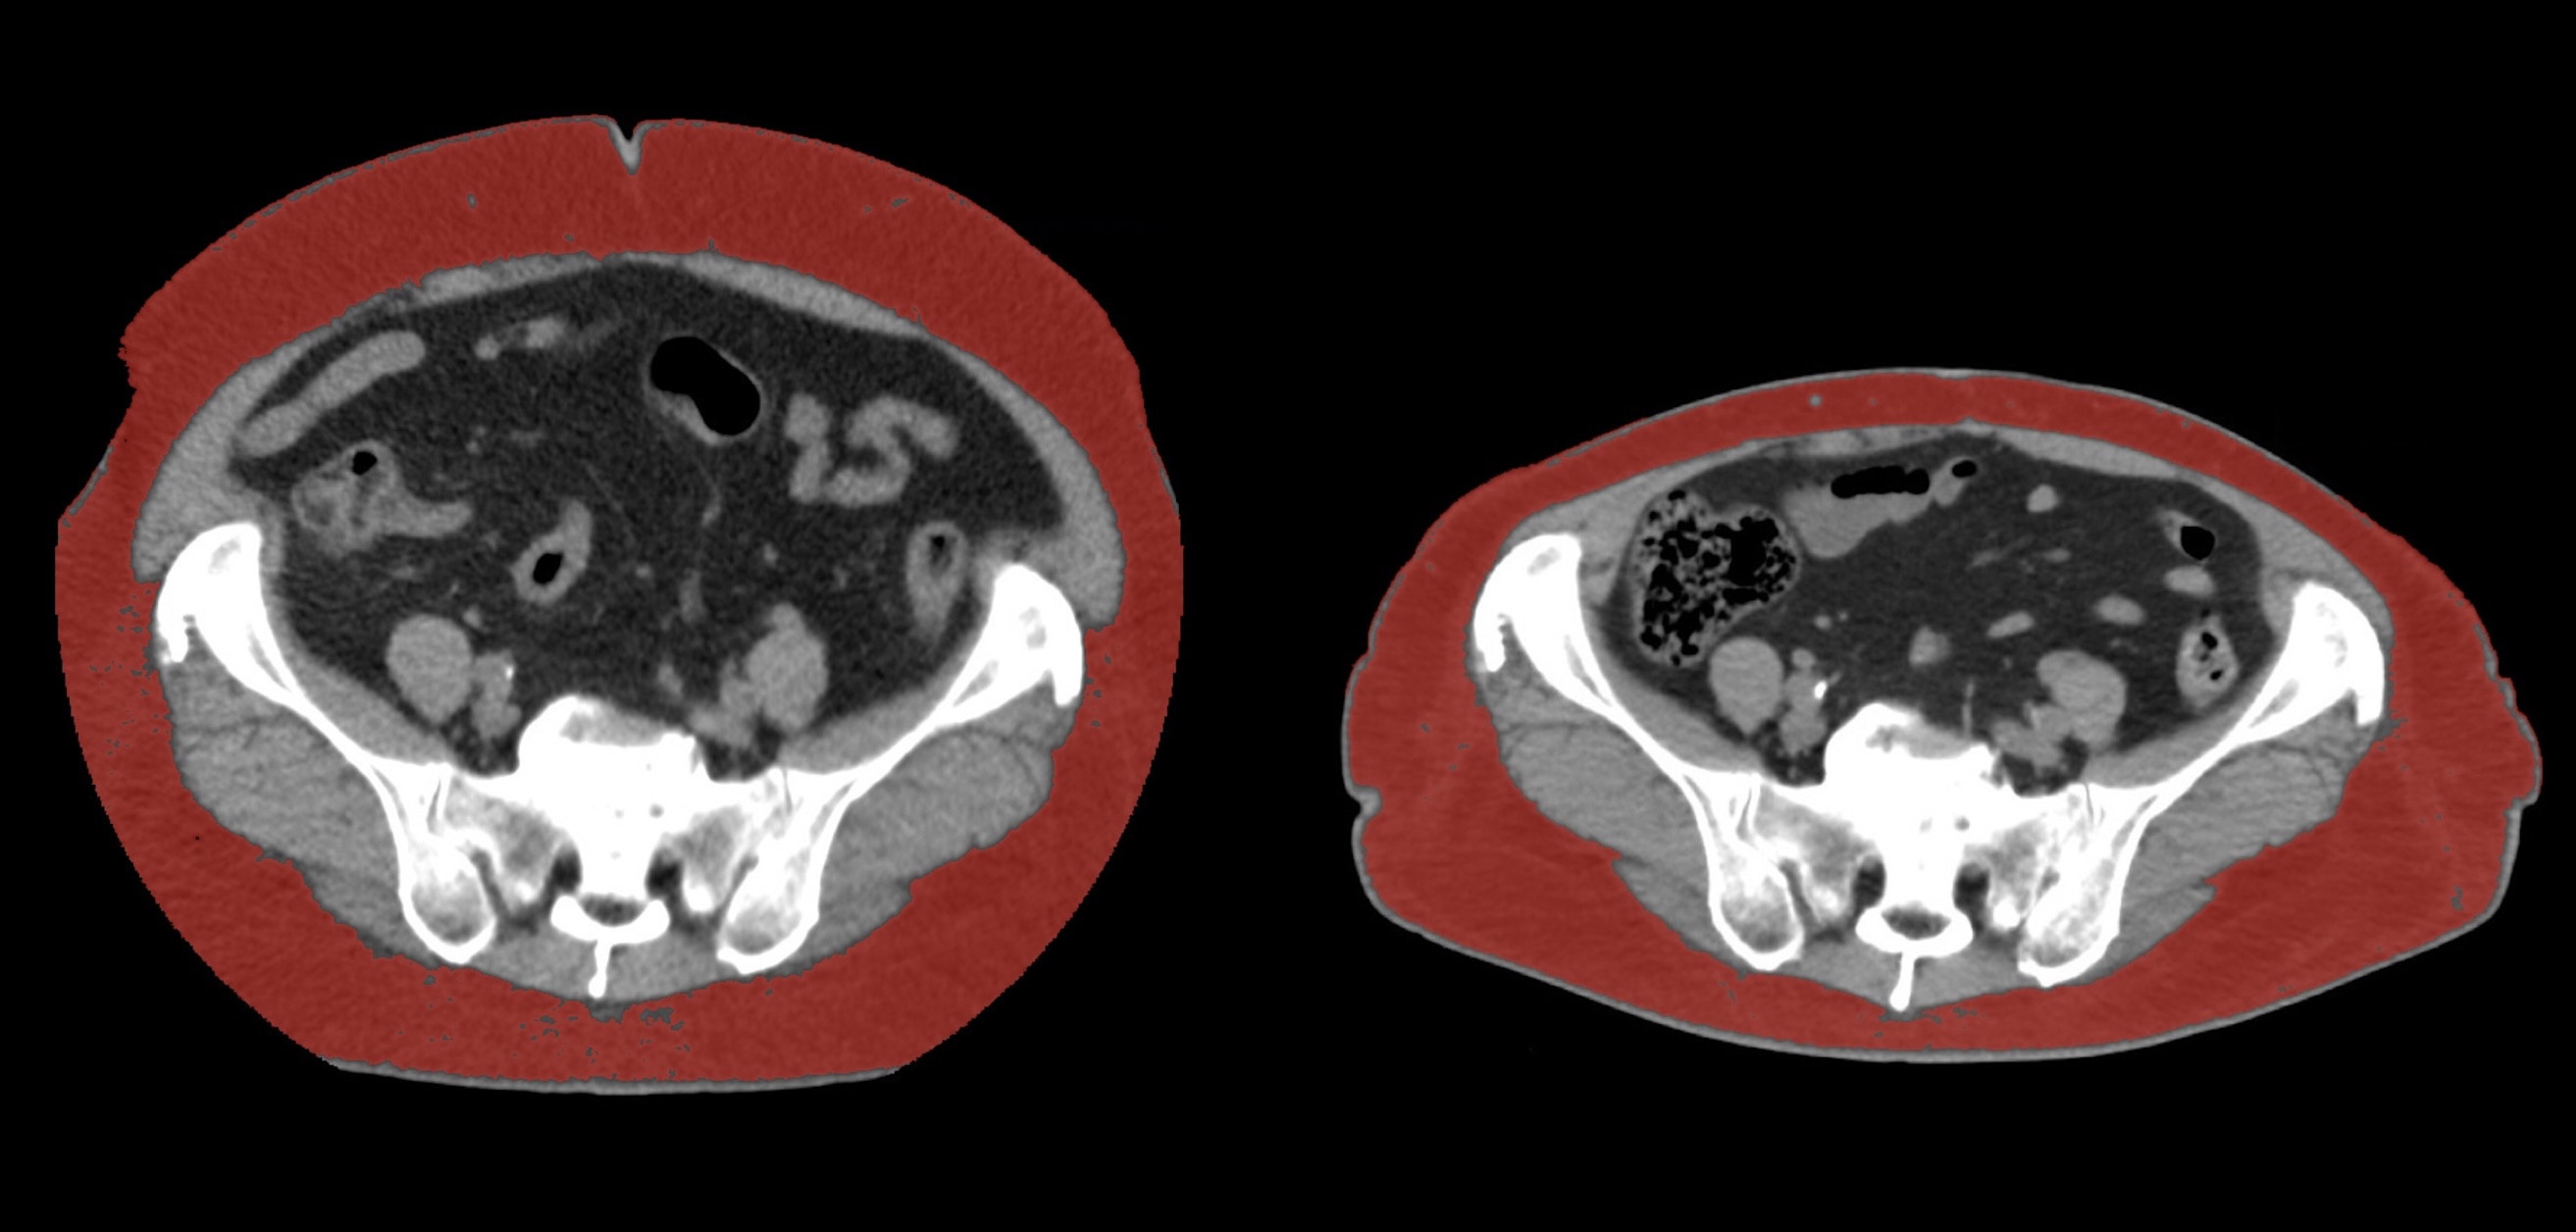

①

50代・女性(ご本人のご厚意で画像提供)

治療内容:チルゼパチド7.5mgの週1回自己注射による脂肪減少と脂肪肝改善

治療期間: 12ヶ月(52週)((用量は2.5mgから開始し最大で15mg。減量効果が得られる必要用量には個人差があります。))

費用:自由診療の場合は9900円(税込)×52(週)=514800円

想定されるリスク・副作用:下記に副作用を記載

※医療広告ガイドラインに準拠して表記

1:脂肪の減少

皮下脂肪の減少(赤色部分)